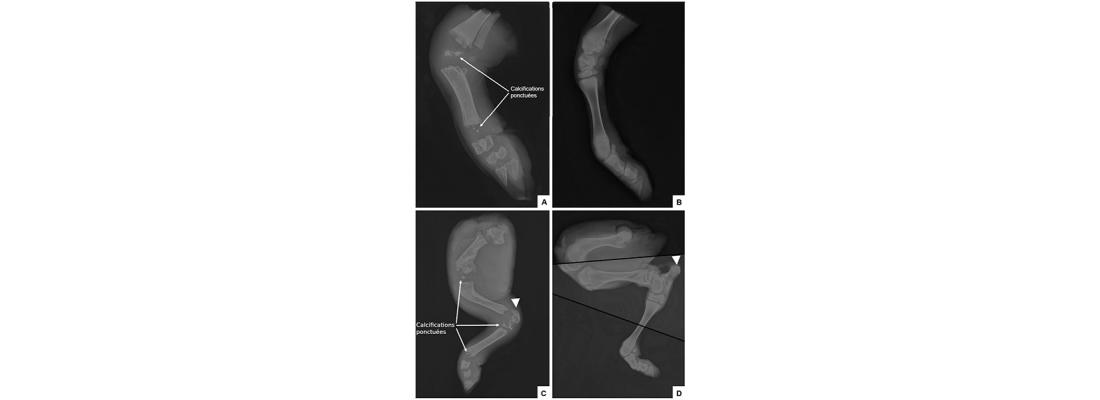

Figure : Radiographie des membres d’un veau atteint de chondrodysplasie ou sain. Membre antérieur d’un veau atteint (A) ou sain (B), membre postérieur d’un veau atteint (C) ou sain (D). Le triangle blanc indique l’emplacement de la tubérosité du calcanéum, absente chez le veau atteint.

Une étude complémentaire chez la race Bazadaise a identifié un variant délétère récessif dans une région codante de PEX7, également associé à une forme létale de chondrodysplasie. Trois veaux Bazadaise affectés présentaient des déformations cranio-faciales et des membres raccourcis très similaires aux veaux Aubrac atteints, confirmant l’intérêt du bovin comme modèle pour explorer les anomalies peroxysomales et squelettiques de la RCDP.